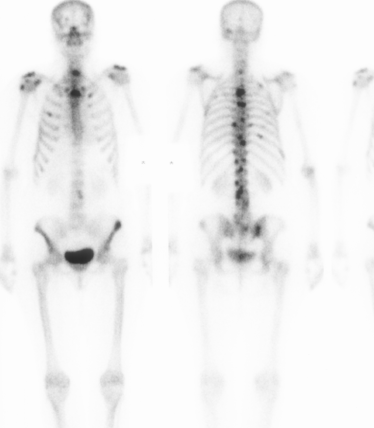

Normal scan

Children

- overall very active

- hot symmetrical epiphyseal growth zones

Adults

- slightly hot at ends of long bones, SI joints, tips of scapulae, nasal cavity

- age related changes (ACJ, DDD)

1. Investigation for bony metastases

95% sensitivity

- multiple scattered focal hot spots in axial skeleton

'Superscan'

- can occur if metastases coalesce